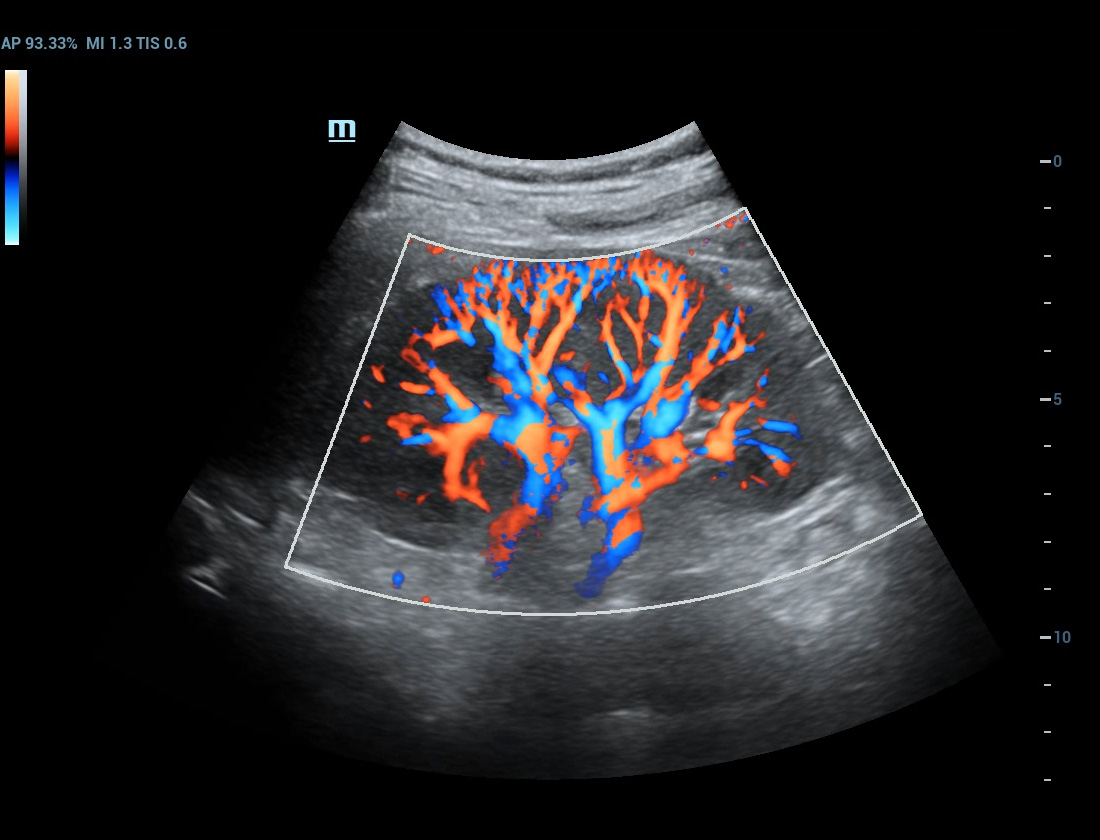

Ultra-micro-angiografie

Breng kleurendoppler op een hoger niveau

Ultra-Micro-angiografie (UMA)

UMA verbetert het diagnostische vertrouwen door de zichtbaarheid van de bloedstromen uit te breiden tot op het kleinste vaatniveau, met een superieure gevoeligheid en resolutie van de bloedstroom.

sUMA Nier

pUMA Borstmassa

sUMA Schildklierkanker

Borstmassa cUMA

Borstmassa

Nier PUMA